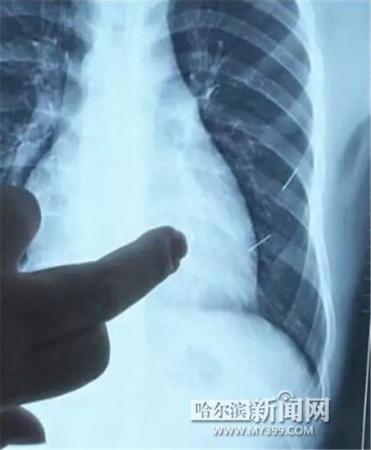

醫(yī)生指出X光片上的針狀物

昨日上午,記者在哈醫(yī)大二院第八住院部心外三病房找到了躺在病床上痛苦不堪的董立仁,家屬正在他身旁不斷安慰著他。見記者前來,董立仁母親李百燕拿出一張X光片,上面可以清晰地看到胸腔內(nèi)一共有4根針狀物,其中一根在心臟部位,兩根在胸腔壁上,還有一根在腹腔壁上。

心外三病房董立仁的主治醫(yī)生告訴記者,董立仁送到醫(yī)院時病情很危險,隨時可能危及生命?!巴ㄟ^檢查發(fā)現(xiàn),他心臟內(nèi)有一個金屬異物,正好在心臟上。心臟每次跳動都與其產(chǎn)生摩擦,導(dǎo)致出血,心包積液懷疑是血液。如果大量出血會凝結(jié)成血塊,血塊包裹住心臟就會影響心臟跳動,隨時都有停跳的危險。心臟上的異物是致命傷,其余胸腔壁和腹腔壁的異物傷害不大。”

昨天16時30分左右取針手術(shù)開始。因鋼針隨時會危及患者生命,此次手術(shù)定義為大型手術(shù)。開胸后,醫(yī)生打開董立仁心包,發(fā)現(xiàn)一枚鋼針已深深扎入心臟,僅露出1厘米長度在外。拔出鋼針后,醫(yī)生發(fā)現(xiàn),這枚針長達(dá)5厘米。受鋼針影響,心包出現(xiàn)大量積液,近800毫升。

隨后,在下胸壁位置,第二枚鋼針順利取出。在尋找另兩枚鋼針過程中,普外、胸外多名醫(yī)生也參與手術(shù),為主刀醫(yī)生提供更為穩(wěn)妥的處理建議。根據(jù)X光片顯示位置,醫(yī)生未在患者體內(nèi)找到剩余兩枚鋼針。醫(yī)生懷疑,其中一枚鋼針可能深藏在肋骨骨膜位置,無法尋找,最后決定結(jié)束手術(shù),做進(jìn)一步觀察,研究下一次手術(shù)方案。